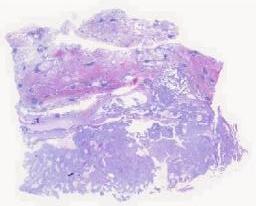

临床资料: 间断痰血1月余

大体所见: 左肺下叶背段病灶。楔形肺组织一块,灰白暗褐,大小8*5*3cm,肺组织表面可见面积3.2*3cm,灰白淡黄似干酪样组织,多切面切开,未见其它病灶。